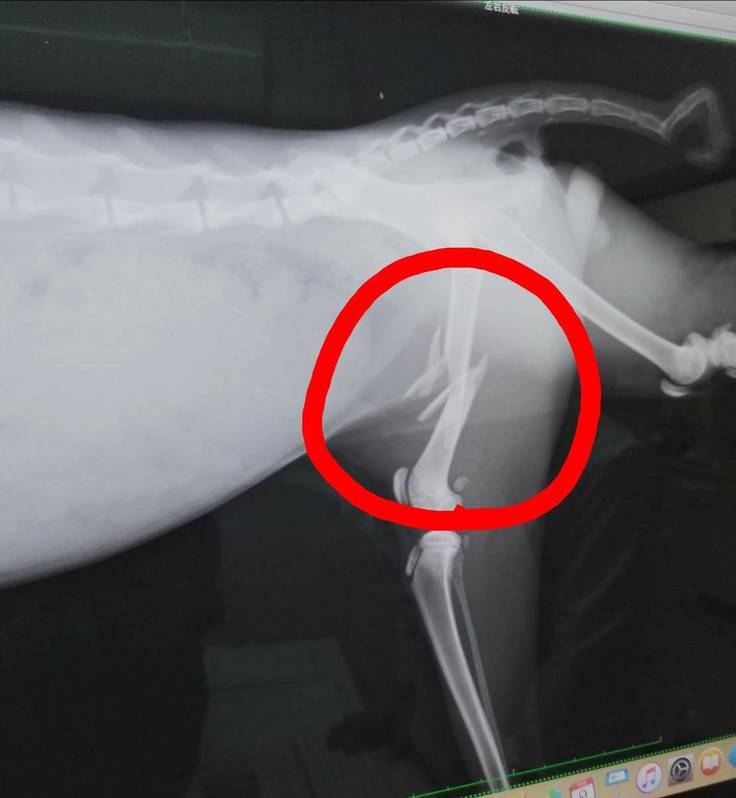

手術次の日の画像です。

●治療・手術内容

事故による左足大腿骨粉砕骨折の手術

入院6日間